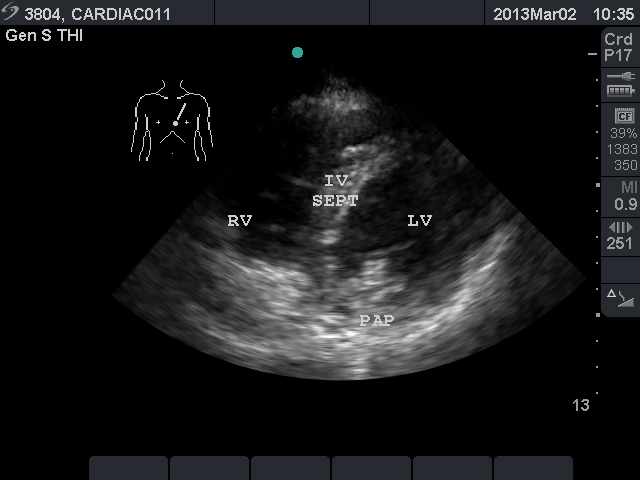

Video 2. Normal parasternal long axis view - Parasternal Short Axis View: This view is a cross sectional view of the left and right sides of the heart. These can be “sliced” at various levels between the base and the apex. By fanning the probe towards the right shoulder, one can visualize the aortic valve in cross section. The “Mercedes Benz” sign shows all three of the leaflets. The right ventricular outflow tract and pulmonary valve can be seen in this view. At the base, the mitral valve is seen inside the left ventricle. At the mid ventricular level, the papillary muscles are seen within the left ventricle. This is the most commonly used parasternal short axis view in point-of-care ultrasound in the acute care setting. At the apex, the left ventricle has tapered and no structures are seen within.

- Figure 3. Parasternal short axis view at the mid ventricular level. RV = right ventricle. IV SEPT = interventricular septum